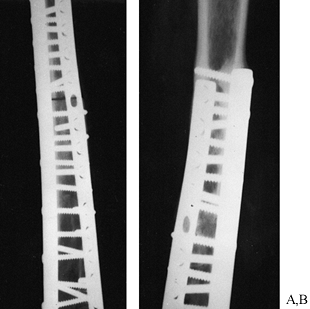

replace missing bone segments and to promote the healing of nonunited

used for filling cysts or cavities (Fig. 9.12); cortical bone is optimal for reconstructing defects that require a certain form and strength (Fig. 9.13).

Although a cortical bone graft is strong when first implanted, the

incorporation process frequently weakens it, so a fatigue fracture may

occur many months to years after implantation (14). Therefore, plates or intramedullary devices are frequently used to augment the strength of the graft during incorporation.